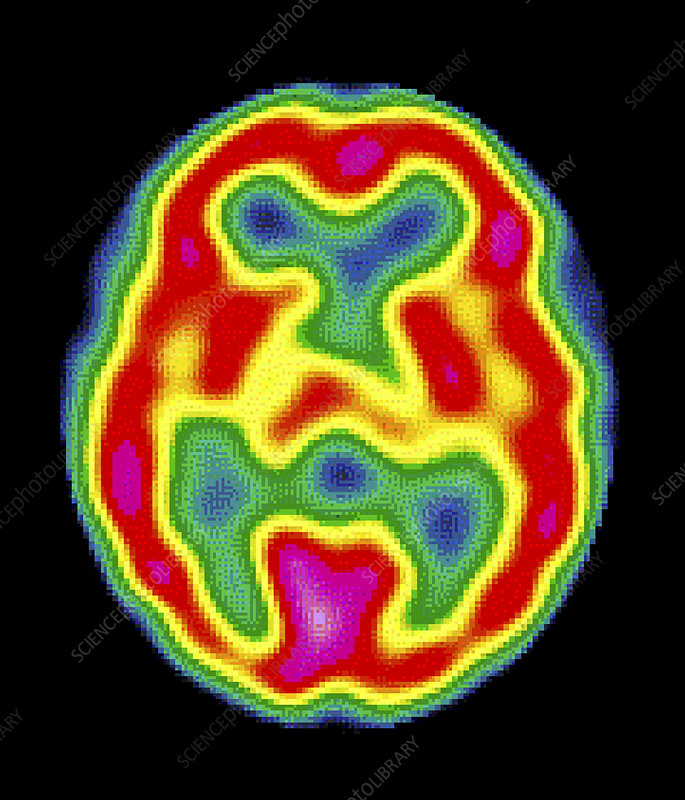

Recently, in Wabie v Wilson (2022 ONSC 4296) the Ontario Superior Court of Justice revisited the role played by SPECT scans in diagnosing Traumatic Brain Injuries (TBIs). SPECT (or Single Photon Emission Computerized Tomography) is a highly specialized form of diagnostic imaging that measures perfusion (the flow of blood) in the brain. As opposed to MRI or CT scans, which are used to view anatomy or structure, the 3D SPECT images show areas of decreased perfusion that highlight abnormalities in brain function.

Justice Sutherland agreed with the plaintiff. After considering the competing expert evidence in detail, he confirmed that, “The SPECT scan looks at the function as opposed to viewing the anatomy/structure as with a CAT scan or MRI. SPECT scans are a secondary test tool. It should not be used as a primary assessment tool.”